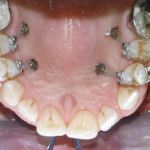

Utilizzo delle miniviti ortodontiche in un caso di riabilitazione implanto-protesica a carico...

Riassunto

In questo articolo viene presentato un caso clinico di riabilitazione implanto-protesica a carico immediato di un’edentulia bilaterale posteriore dell’arcata inferiore caratterizzata da riduzione dell’altezza...